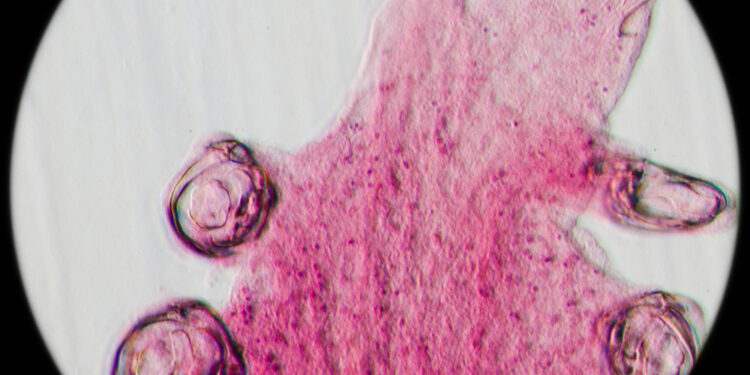

Jei gydytojui kyla įtarimas dėl kabliarplės, skiriamas išmatų tyrimas – per mikroskopą ieškoma parazitų kiaušinėlių. Jei asmuo neseniai lankėsi vietovėje, kur kabliarplės paplitusios, gali būti paskirti ir kraujo tyrimai – pavyzdžiui, nustatyti padidėjusį tam tikrų baltųjų kraujo kūnelių kiekį (eozinofiliją), kuris būdingas šiai infekcijai. Neretai kraujyje pokyčiai išryškėja dar prieš pasirodant kiaušinėliams išmatose.